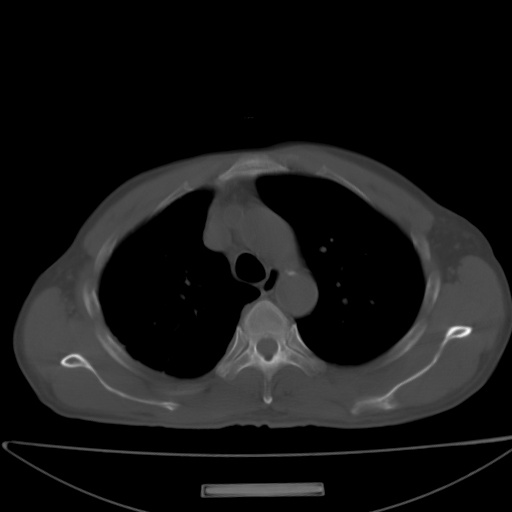

以下是引用jsgdoctor在2008-11-6 22:12:00的发言:[br]右主支气管壁明显增厚,管腔狭窄.考虑为右侧中央型肺癌伴阻塞性炎症\\肺脓肿.

以下是引用zjzjr在2008-11-6 20:25:00的发言:[br]中心型肺ca,合并阻塞性肺炎

以下是引用zsl6918在2008-11-6 19:43:00的发言:[br]右侧中心性肺癌(鳞癌)